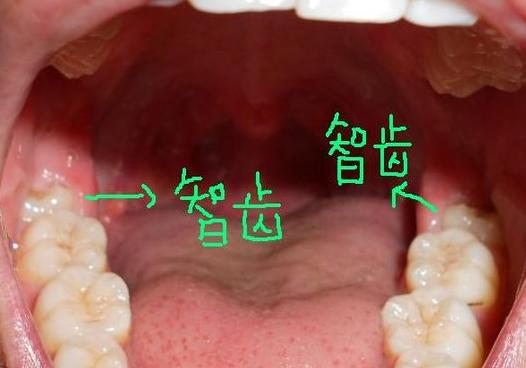

智齒冠周炎的癥狀是怎樣的?智齒是牙列中最后萌出的,常常發(fā)生阻生,如果智齒萌出不全或萌出受阻,就容易導(dǎo)致牙冠周圍組織發(fā)生炎癥。一般以下頜智齒最多見,臨床上分為急性和慢性兩種。發(fā)病初期,常有全身誘發(fā)因素,并帶有輕微癥狀,很容易忽視而耽誤治療。那么,智齒冠周炎的癥狀是怎樣的?>>>點擊免費咨詢,或者撥打24小時牙齒健康熱線05962557333咨詢,漳州附屬口腔醫(yī)院專家為您解答!

智齒冠周炎的癥狀是怎樣的?智齒冠周炎讓人們痛不可言,我們應(yīng)該先了解一下智齒冠周炎的癥狀,以便做判斷。